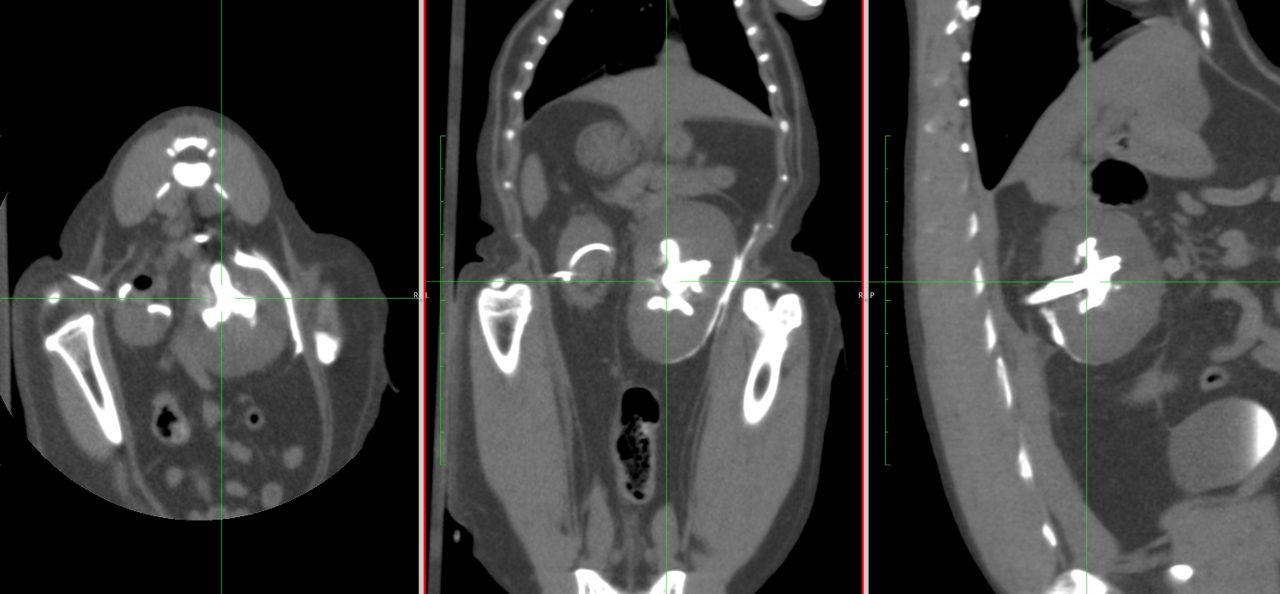

急性腎機能障害の猫ちゃんが(BUN>130mg/dl、Cre>14mg/dl、高カリウム血症)治療のため救急で対応しました。無麻酔CTでは両側に尿管結石が確認されました。著しく拡張している左腎の腎盂に一時的な腎瘻カテーテルを設置し、尿の排泄路の確保を行います。しかし、腎数値に改善は見られませんでした。腎盂造影を行うと拡張している腎臓において尿の産生と排泄は行われている様です。一方、腎盂拡張のほとんどない右腎の腎盂造影では尿の排泄が確認されません。今回の急性腎機能障害の原因は機能の残っていた右腎の急性尿管閉塞による急性腎障害と診断しました。左腎に関しては尿の産生はあるものの慢性腎機能障害であり、すでに尿濃縮能は失われていると判断しました。右腎の問題に対して尿管膀新吻合短尺型ステント設置術を行いました。術後は徐々に腎数値は低下し、腎機能の回復が得られました。一見すると腎盂拡張の顕著な側が急性腎障害の責任病変と判断しがちですが、片腎が十分に機能していれば腎数値に影響はほとんどなく、どちらの腎臓を治療対象とするか?エコー、CTなどの画像診断、血液検査、一時的な腎瘻カテーテルの設置、腎盂造影など総合的な判断が必要です。また判断がつかず、左右同時に治療が必要な場合もあります。